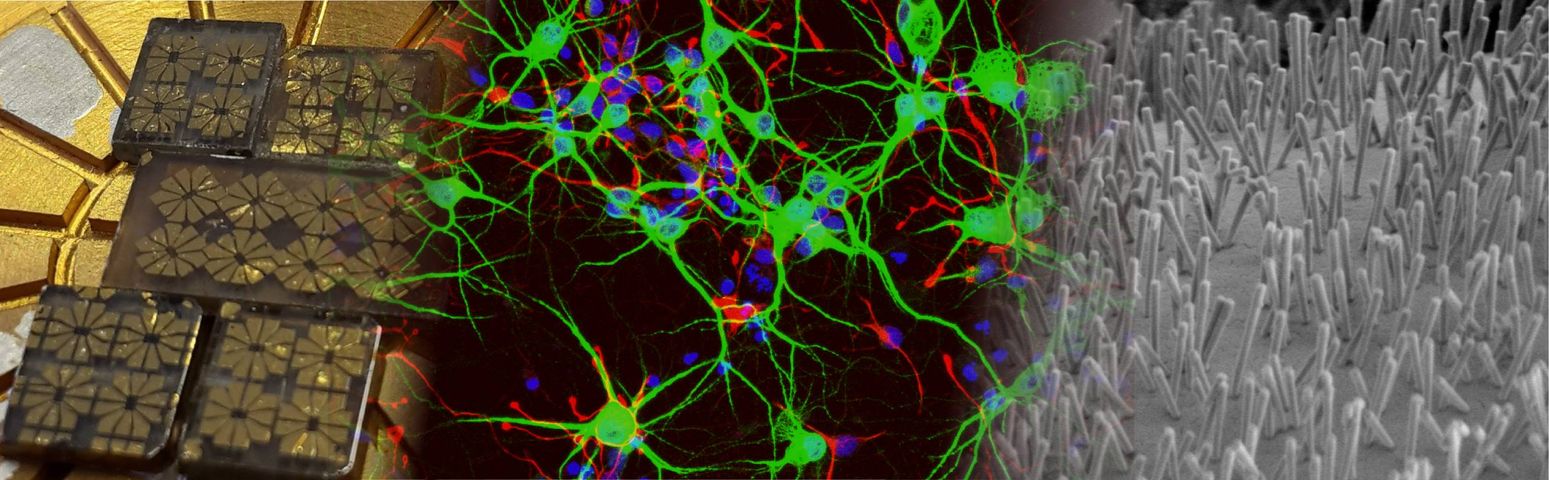

Graphene-based drug delivery device for mucosal and transmucosal administration

DEVICE FOR MECHANICALLY STIMULATING BIOLOGICAL MATERIAL AND ITS PROCEDURE

FLEXIBLE DEFORMABLE SHEET STRUCTURE